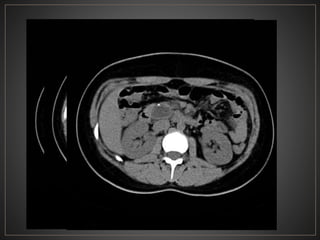

• 48.

CPRE: Dilataciones saculares de CBIH. TC: Simple:Áreas redondas, hipointensas en topografía de CBIH. Contraste: Signo del punteado central. RM: T2: Espacios quísticos hiperdensos